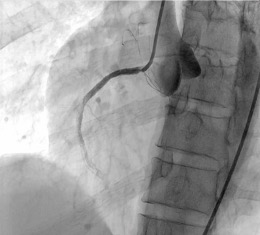

Procedural Step

Percutaneous coronary intervention was initiated. A Xience Alpine 3.0 x 38mm drug-eluting stent (DES) was positioned at the mid to distal RCA and deployed at 16 atm and post-dilated using the same stent balloon inflated at 18 atm. Another Evermine 3.5 x 48mm drug-eluting stent (DES) was positioned at the proximal RCA and deployed at 18 atm and post-dilated using the same stent balloon inflated at 18 atm. Further dilation of the distal RCA was done using a Mini Trek 2.0 x 15mm balloon and inflated at 12 atm. However, j ust a few minutes after placing the stent. There was noted recurrence of the ST elevation on the cardiac monitor. A second look angiogram was immediately performed to check the patency of the stents. Immediately, manual distal displacement using the same stent balloon was done to displace the thrombus. Repeat angiogram showed TIMI II flow on the right coronary artery and resolution of the ST segment elevation.